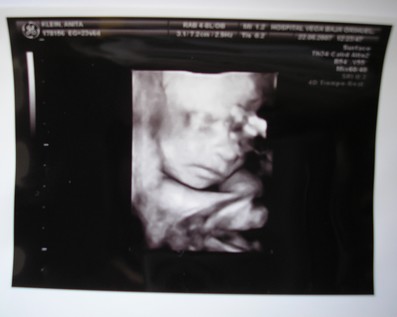

Ma kora reggel megszülettek a kicsi fiúk, róluk hoztam képeket nektek. Éjfél körül szivárgott a huginál a magzatvíz, felhívták a kórházat, ott mondták, inkább menjenek be, az a biztos. Kapott antibiotikumokat, de sajnos beindult a szülés. 4.32-kor megszületett a Bálint, 1990gr és 44cm, valmint 4.39-kor a Kristóf 2170gr és 44cm. Valami tüdősegítő oxigént kapnak, a Bálintnak sűrű volt a vére, de úgy néz ki, hogy helyre áll magától. Amint megindul a teje kiveheti őket szoptatni, talán 1 hetet kell bent lenni.

Kép

Ő a Kristóf.

Ő pedig a Bálint.